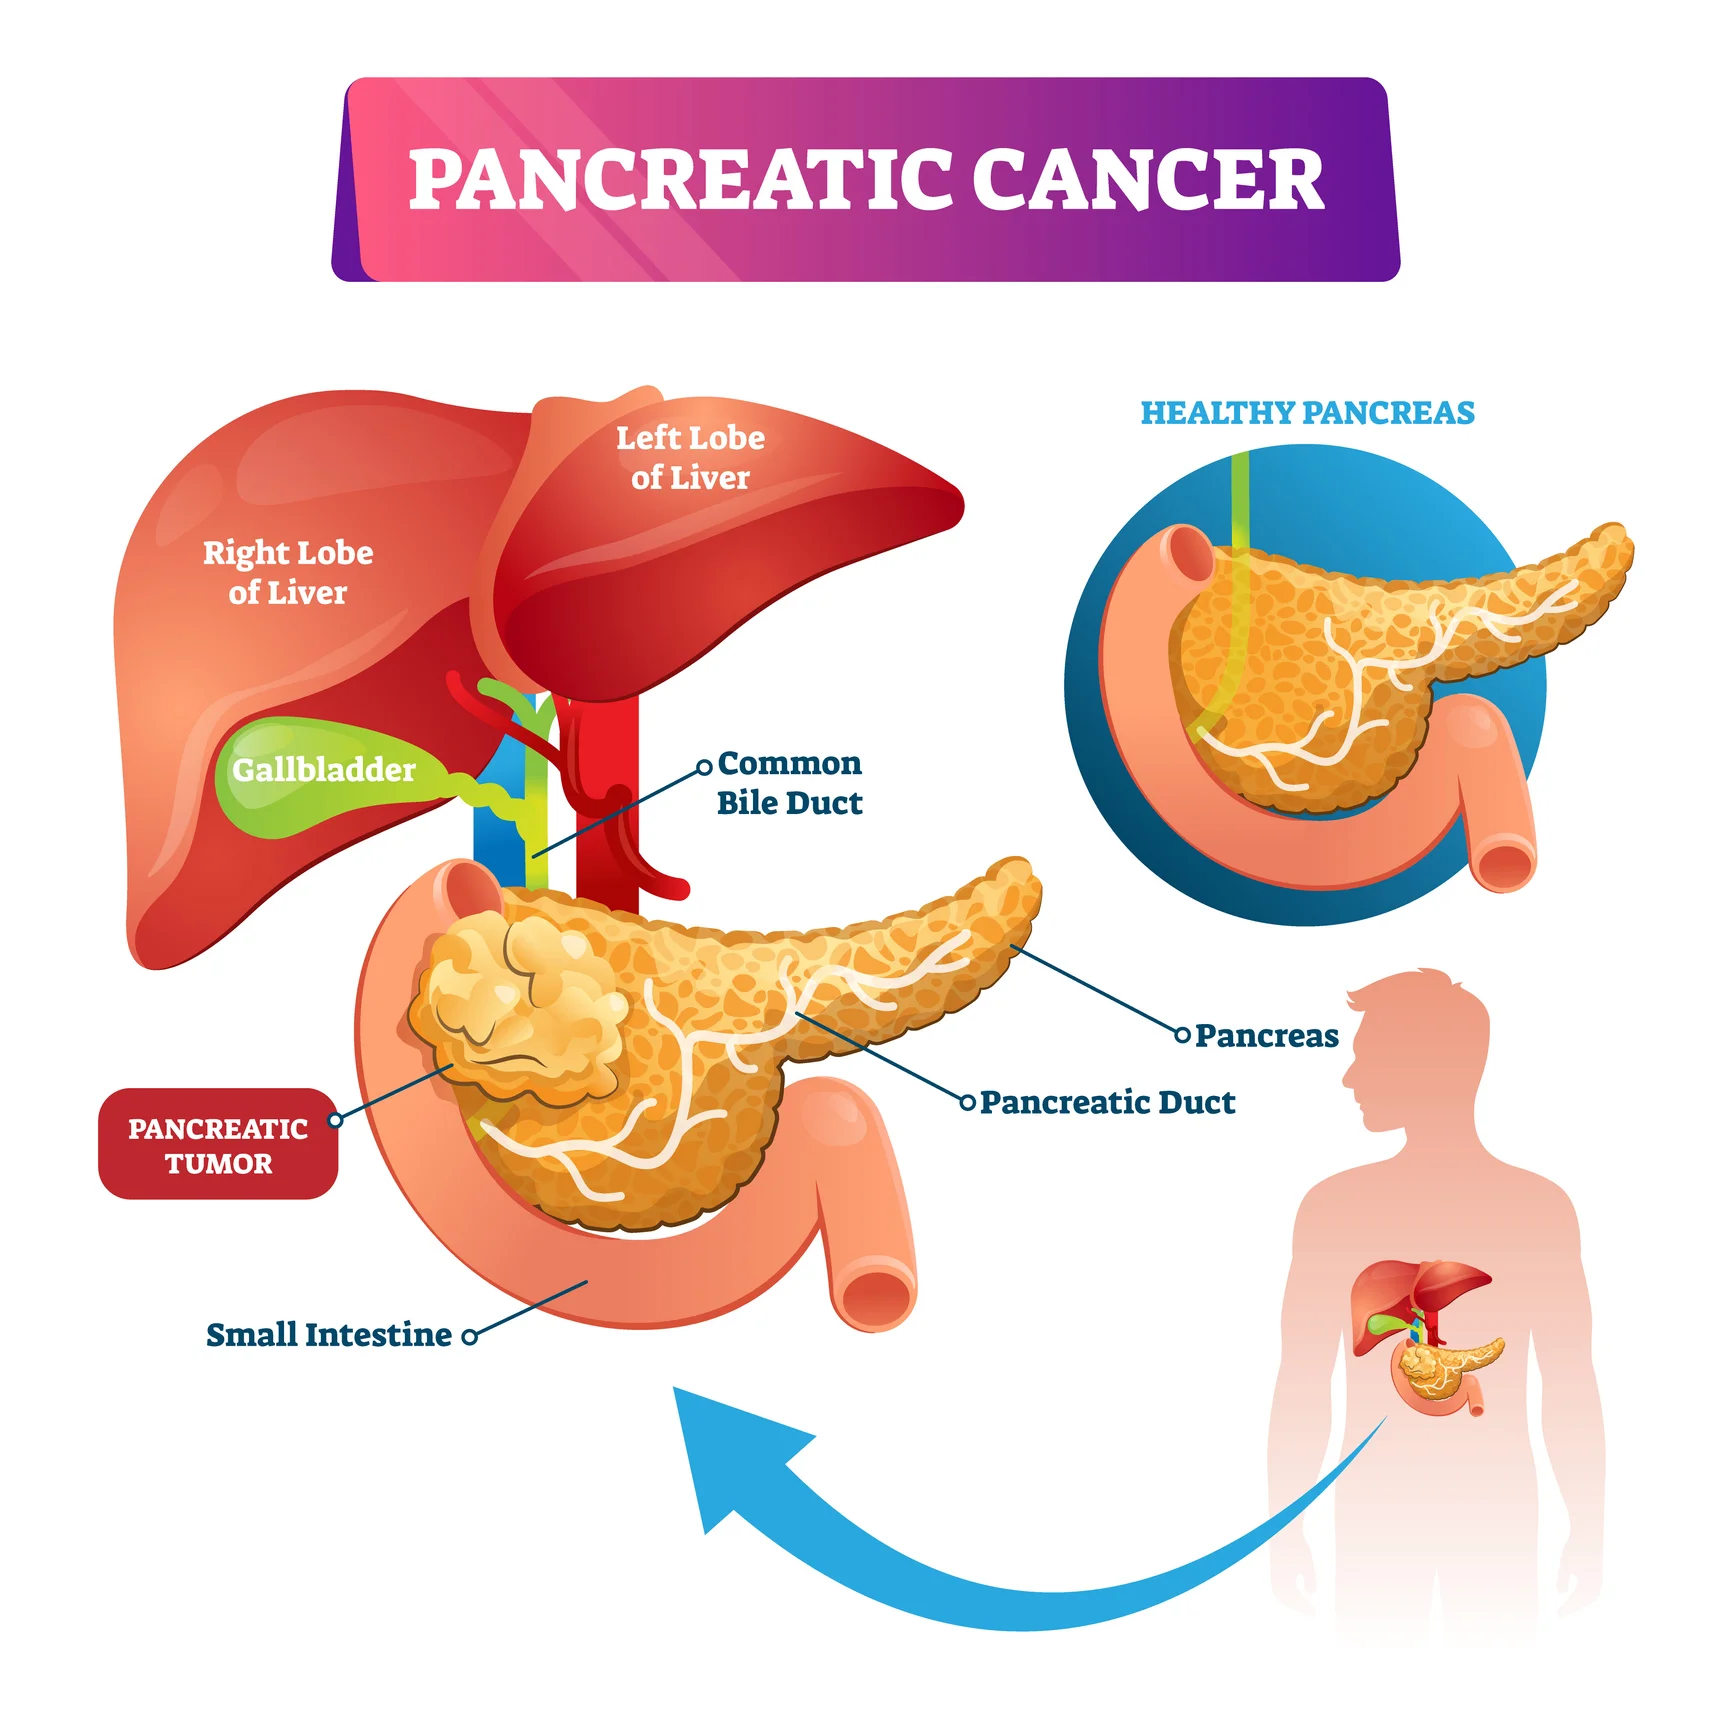

1. Overview

What is Pancreatic Cancer?

Pancreatic cancer is a type of cancer that starts in the pancreas, an organ that plays an important role in digestion and blood sugar control. It develops when pancreatic cells grow abnormally and form a tumor.

Because the pancreas is located deep inside the abdomen, early pancreatic cancer symptoms are often mild or unclear. As a result, pancreatic cancer is frequently diagnosed at a later stage.

Pancreatic cancer is a type of cancer that starts in the pancreas, an organ that plays an important role in digestion and blood sugar control. It develops when pancreatic cells grow abnormally and form a tumor.

Because the pancreas is located deep inside the abdomen, early pancreatic cancer symptoms are often mild or unclear. As a result, pancreatic cancer is frequently diagnosed at a later stage.

2. Where It Begins

Which part of the body is involved?

The pancreas is a small gland located behind the stomach and close to the liver and intestines. It performs two key functions:

● Releases digestive enzymes to help break down food

● Produces hormones such as insulin to regulate blood sugar

Most pancreatic cancers begin in the ducts that carry digestive enzymes.

The pancreas is a small gland located behind the stomach and close to the liver and intestines. It performs two key functions:

● Releases digestive enzymes to help break down food

● Produces hormones such as insulin to regulate blood sugar

Most pancreatic cancers begin in the ducts that carry digestive enzymes.

4. How It Develops

How does pancreatic cancer usually develop?

In a healthy pancreas, cells grow and divide in a controlled manner. In pancreatic cancer, damaged cells begin to multiply uncontrollably and form a tumor.

Over time, the tumor may interfere with digestion, block bile flow, or spread to nearby or distant organs.

The main biological types include:

● Pancreatic adenocarcinoma – the most common type

● Pancreatic neuroendocrine tumors (NETs) – rarer and often slower growing

In a healthy pancreas, cells grow and divide in a controlled manner. In pancreatic cancer, damaged cells begin to multiply uncontrollably and form a tumor.

Over time, the tumor may interfere with digestion, block bile flow, or spread to nearby or distant organs.

The main biological types include:

● Pancreatic adenocarcinoma – the most common type

● Pancreatic neuroendocrine tumors (NETs) – rarer and often slower growing